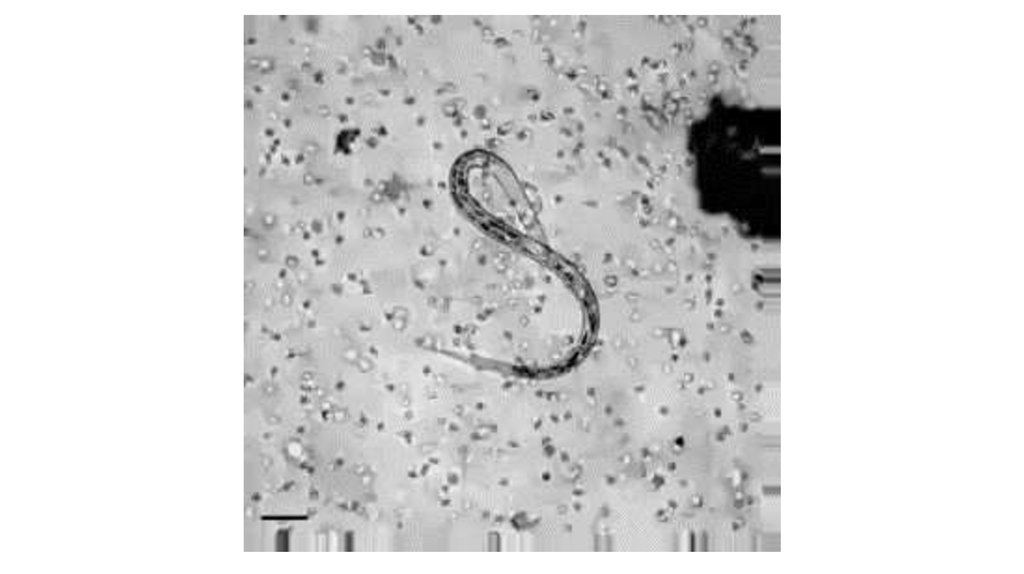

Нетоз у нейтрофилов